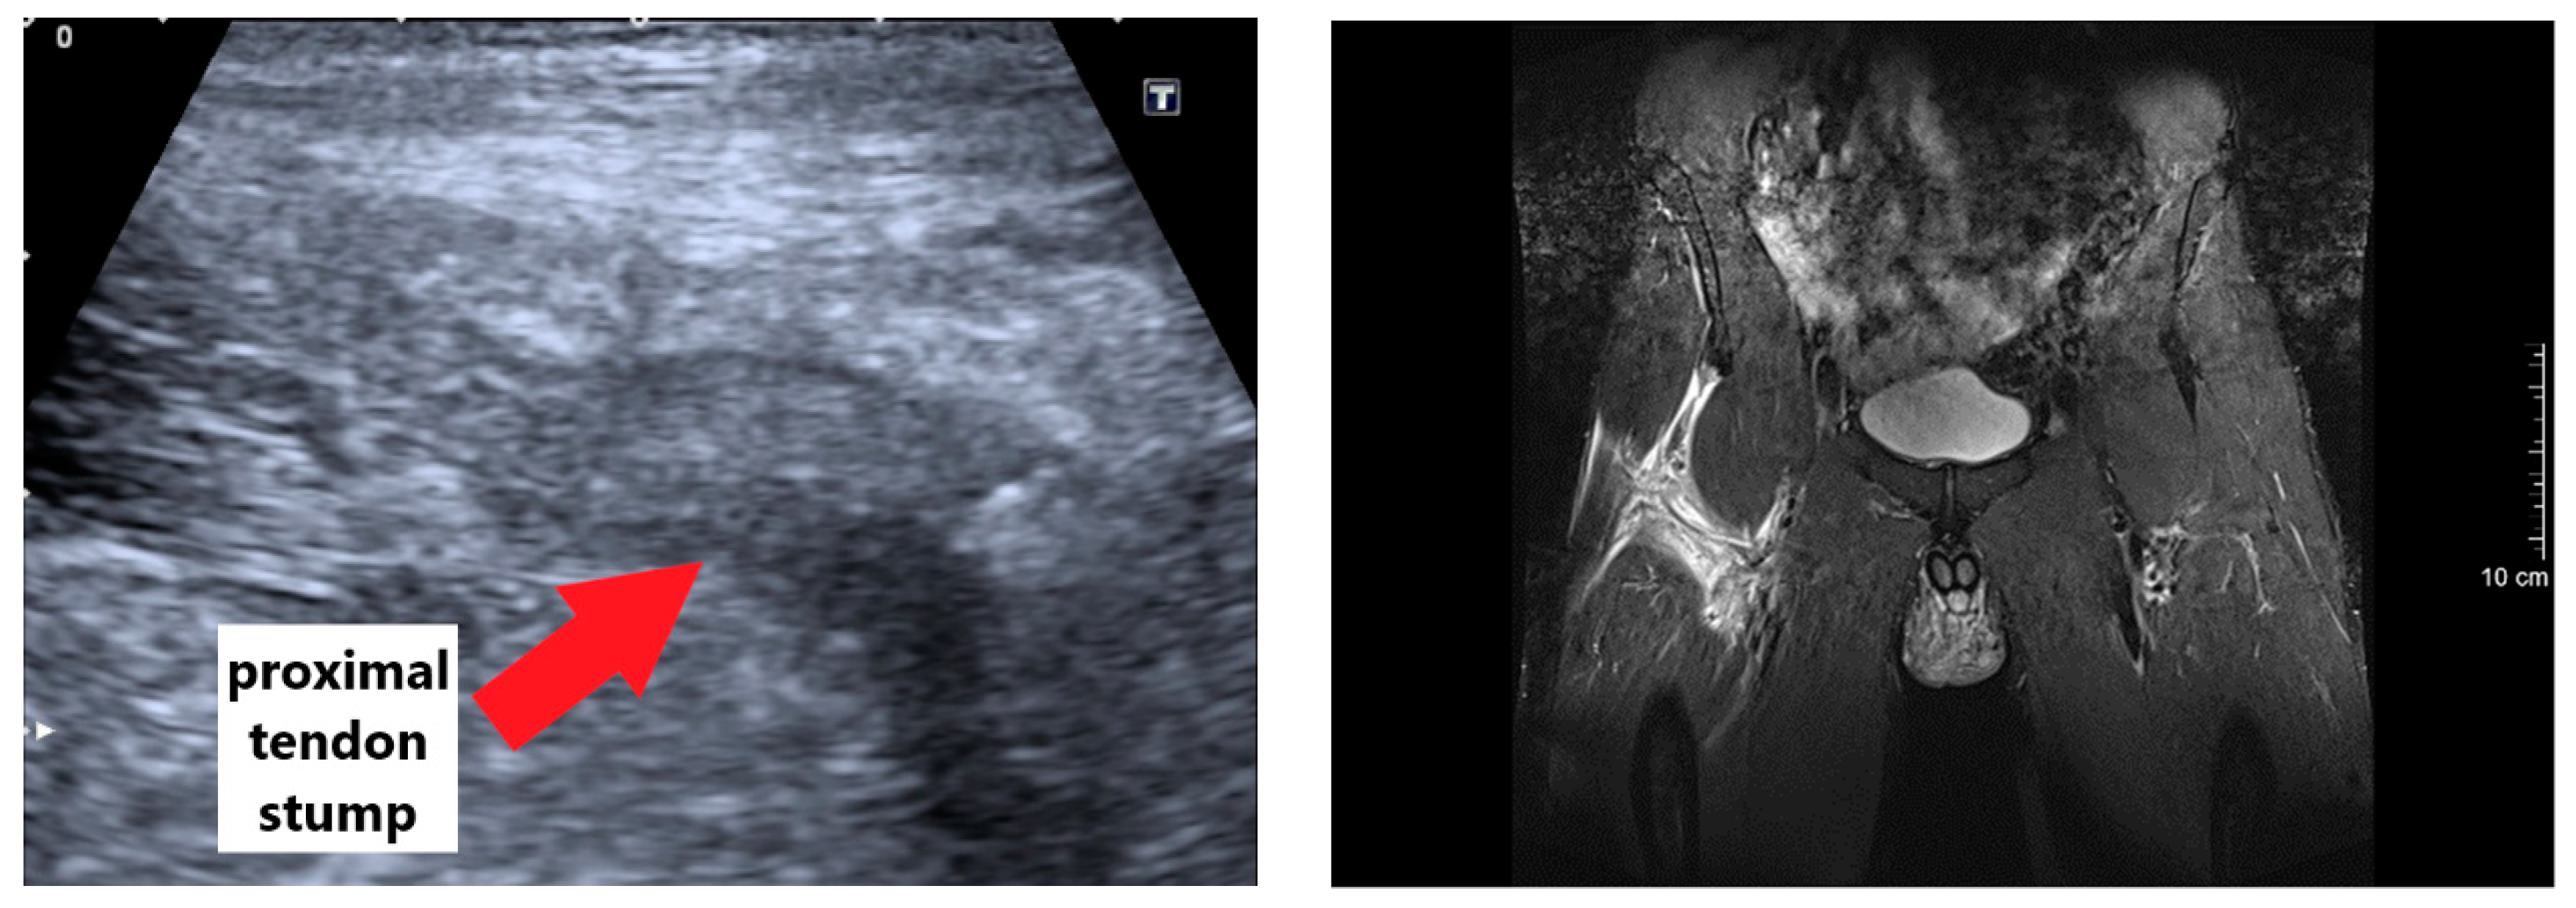

2.2. Diagnosis and Surgery Procedure